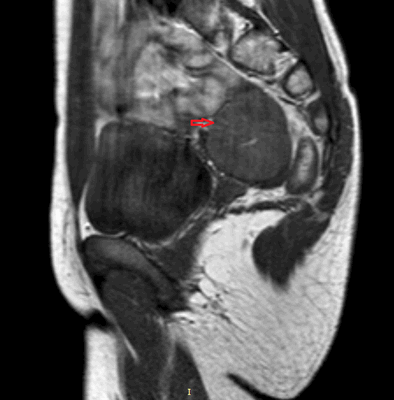

На данном УЗИ представлена больная с симптомом Тернера 45ХО матка нормальных размеров, цервикальный канал норма, полость матки норма, матка с нормальными пропорциями тело/шейки, яичники тяжисты без созревающих фолликулов.

МРТ, Т2-взвешенные последовательности демонстрируют тяжистые матку и яичники ( стрелки ), короткое влагалище ( V ), расположенное между прямой кишкой ( R) и уретрой (Ur ).